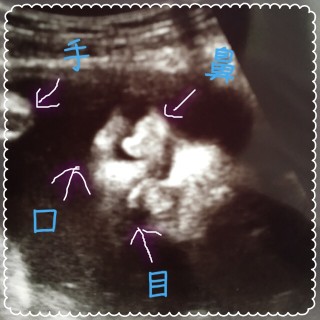

30w1d! BaByくん、 重さ1367g前回より+265g大きくなってました。 先生からゎ平均的だから大丈夫!と言われました。 エコー写真ゎ途中で寝てしまったBaByくんです。 最近ゎジブリのオルゴールのBGMを お腹の↑で流してあげたら、めっちゃ動いてくれます!